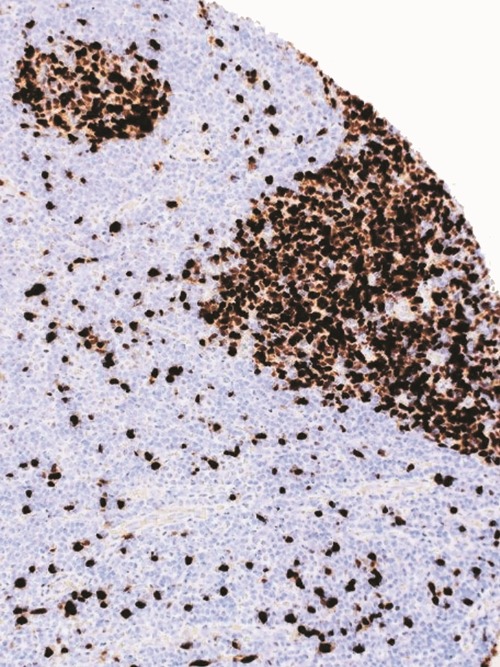

Immunohistochemical staining of human tonsil tissue using TOP2A Mouse Monoclonal Antibody (ARM581).